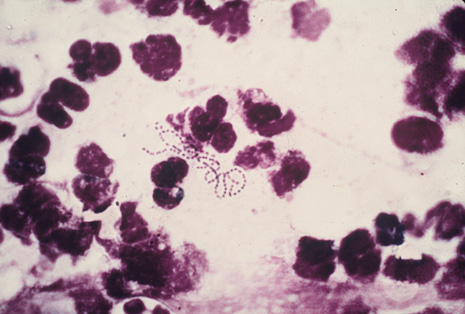

Many forms of uveitis are characterized by specific types of inflammatory cells. Usually, however, one encounters mixtures of cell types in any given specimen, with the relative percentages of lymphocytes and polymorphonuclear leukocytes varying. There may be unusual numbers of eosinophils, or macrophages laden with lens material may be present. Thus, an enumeration of the cells and a careful analysis of their structure can be useful as a diagnostic aid (Figs. 7, 8, 9, 10, 11, 12, 13, 14, 15, 16, 17, 18, 19, and 20). Figure 15 demonstrates eosinophils that were aspirated from the anterior chamber of a patient with Toxocara canis endophthalmitis. Figure 12 demonstrates malignant cell infiltrate from the vitreous, showing the stained presence of monoclonal light chains being elaborated in the cytoplasm. Interleukin-10, detectable in the vitreous of intraocular lymphoma patients, is also directly indicative of both the clinical activity and the number of malignant cells as observed by cytopathology.

Precise identification and culture of bacterial and fungal pathogens from both the aqueous humor and the vitreous fluid can be obtained. Gram's stain and Giemsa's stain smears of centrifuged specimens from the aqueous humor and the vitreous humor frequently demonstrate the bacterial or fungal causative agent. Attempts to isolate bacteria and fungi and to identify them on Gram's stain or Giemsa's stain smears have been most rewarding in the following cases: (a) postoperative endophthalmitis, (b) infection after a penetrating injury of the eye, (c) drug abuse patients with endogenous endophthalmitis (Figs. 21, 22, 23, 24, and 25), (d) patients receiving hyperalimentation, and (4) patients who are immunocompromised as a result of exogenous immunosuppressive agents.